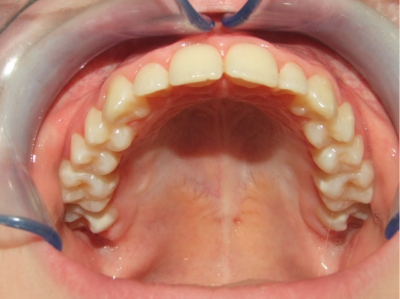

Behandeling Heleen

eindfoto

14-26 volledig vast boven- en onderkaak + TPA

Leeftijd bij retentie: 11 jaar